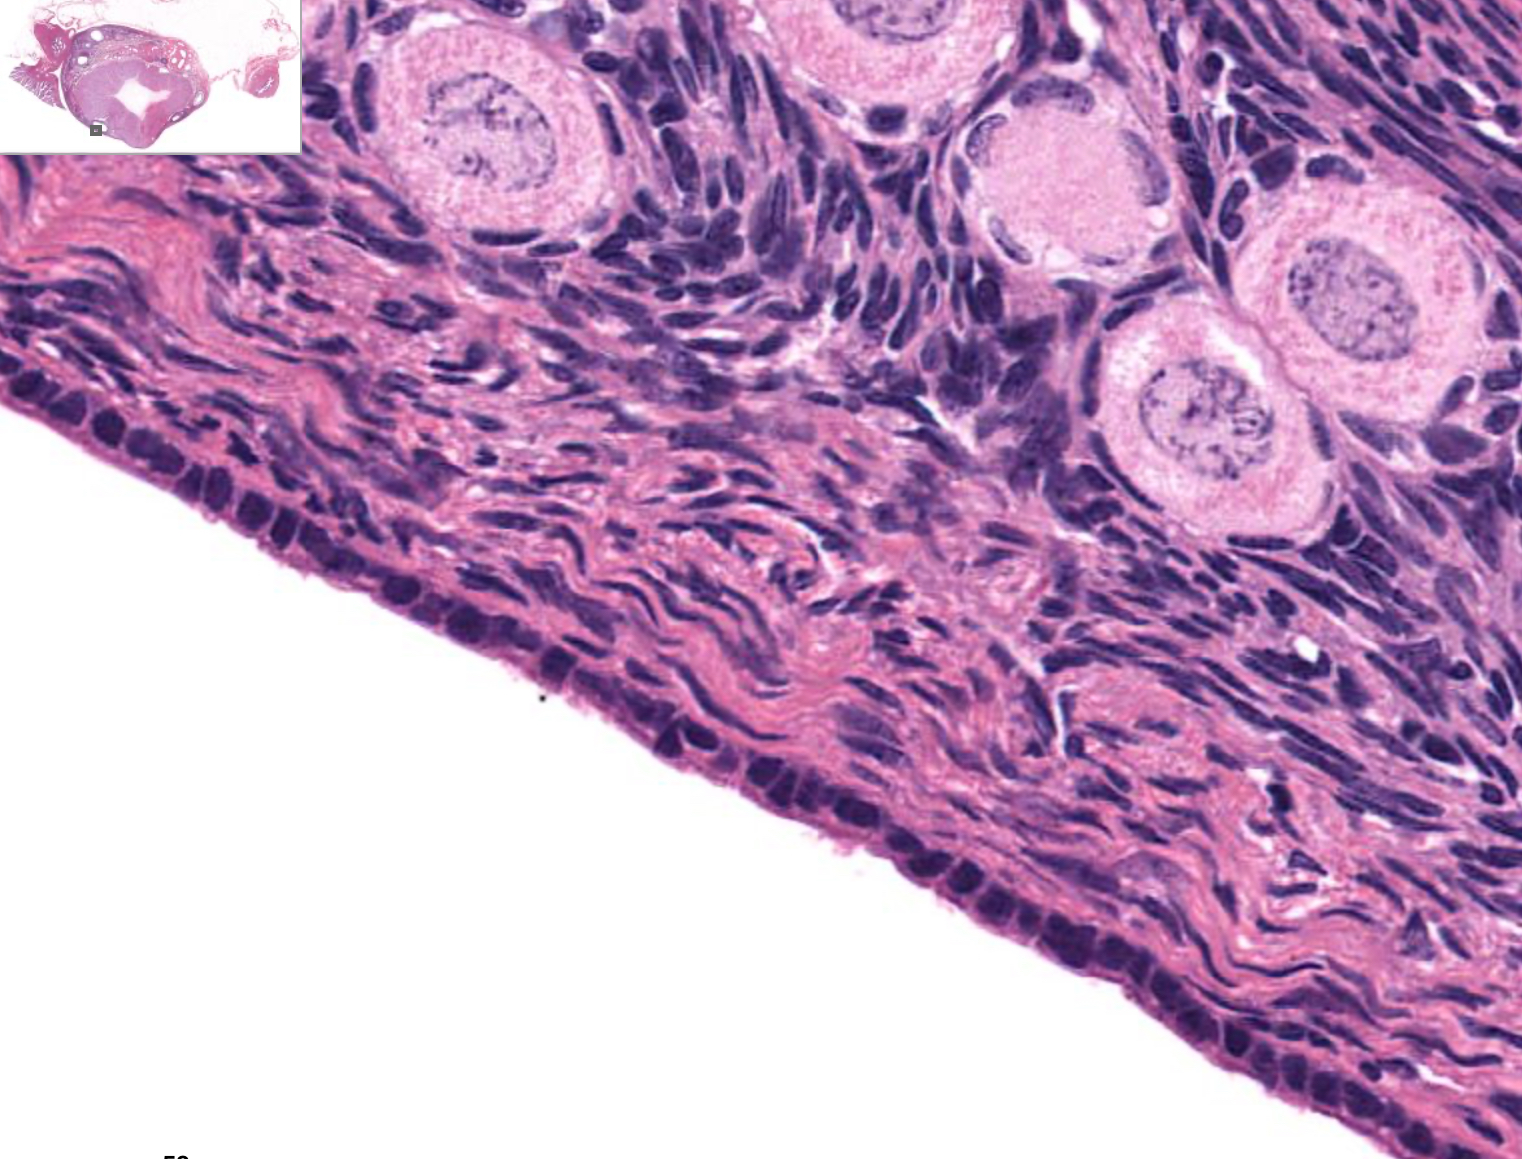

term image

Tissue: nonkeratinized stratified squamous epithelium

Location: anterior surface of cornea

Function:

• protects underlying tissues in areas subject to ABRASION

• surface is exposed to air and is non-keratinized, the epithelium must be kept constantly moist with tears.